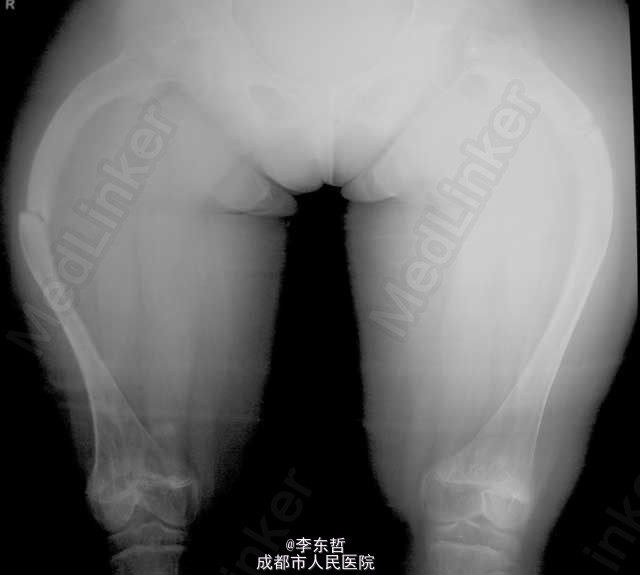

少女成骨不全且伴骨折

患者为12岁女孩,有家族史,曾多次骨折,平日扶双拐,1天前摔倒致双股骨干骨折。

成骨不全症合并股骨干骨折一例

右股骨骨折,成骨不全一例